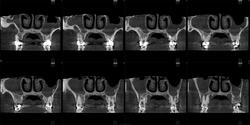

Здравствуйте, коллеги! Представляется КЛКТ ППН. Больной 31 г., направлен ЛОР-врачом на исследование ППН. В левой верхнечелюстной пазухе - костный фрагмент? Аномалия?

Если это отломок, то откуда отвалился. Возможно строение пазухи или остеома. Согласен с Любовью, нужны дайкомы.

На серии изображений прослеживается в задних отделах левой (? ) верхнечелюстной пазухи септальная структура ( вариант строения ), острый синуит ( гайморит), фаза эксудации.

Согласна с Аlmo, как вариант строения

Возможно, имеет место не костная, но хрящевая связь. Добавочная септа/перегородка - на мой взгляд, оптимальный вариант. Губчатая остеома выглядит здесь не то что редко, просто незнакомо. На зубик не совсем похоже. Вернее, совсем по-моему не похоже.)